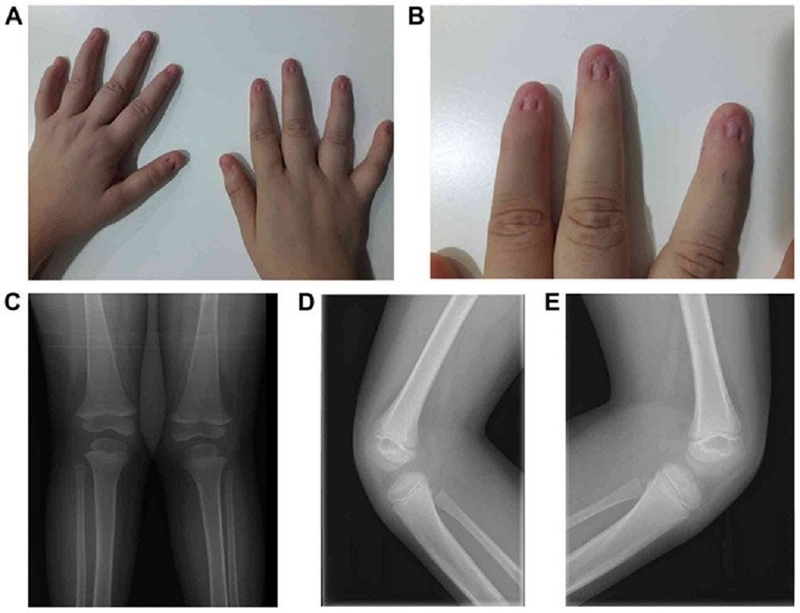

Một số lượng lớn bệnh nhân (93 - 98%) thường trải qua loạn dưỡng móng ngay từ khi mới sinh, đặc biệt là ở ngón cái và ngón trỏ (móng chân ít bị ảnh hưởng hơn). Móng tay của bệnh nhân có thể thể hiện các đặc điểm như kém phát triển hoặc thiếu, thay đổi màu sắc, chẻ ngọn, có rãnh hoặc rỗ.

Đến 92% bệnh nhân có thể trải qua các biểu hiện của thiểu sản xương bánh chè từ mức bất sản đến giảm sản. Điều này thường thấy qua những đặc điểm như hình dạng không bình thường của xương bánh chè (rời từng mảnh hoặc hình đa giác), kích thước nhỏ hoặc thiếu, khớp không ổn định, dễ bị trật và đau khớp, lồi cầu xương đùi gây ra sai khớp xương bánh chè.

Khoảng 90% bệnh nhân thường trải qua loạn sản khuỷu với đầu xương quay biến dạng, đầu xa xương cánh tay dễ gây bất thường trong khớp khuỷu, hạn chế động cơ của tay như khả năng ngửa cẳng tay hay di chuyển khuỷu, gập khuỷu. Khuỷu tay của bệnh nhân cũng có thể hướng ra ngoài, tăng nguy cơ trật khớp.